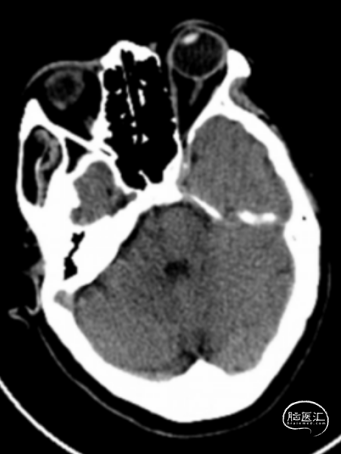

术前头颅CT示:颅内未见明显异常。

术后24小时头颅CT:右侧基底节区少量出血及低密度灶。